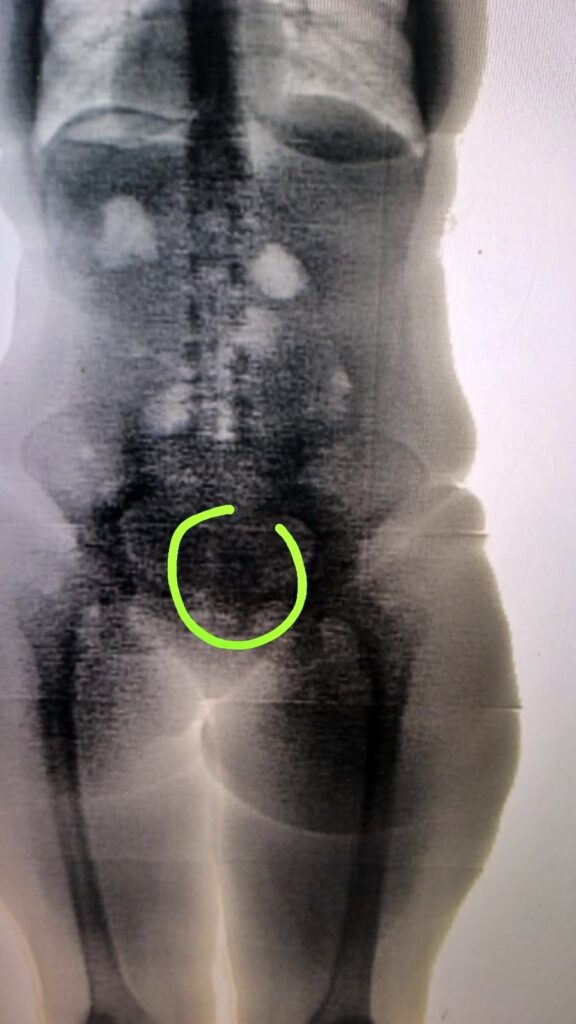

Policiais penais que atuam no plantão deste sábado (29) na Penitenciária de Segurança Máxima de Alagoas (PenSM) flagraram, durante inspeção de rotina, uma mulher de 37 anos que tentou entrar na unidade prisional com drogas escondida dentro do corpo.

O entorpecente - que seria entregue ao companheiro dela, reeducando que cumpre pena na PenSM - foi detectado com o auxílio do bodyscan, que faz varredura corporal interna.

"Assim que observamos algo estranho nas imagens do bodyscan, iniciamos os procedimentos para confirmar a presença do que seria um ilícito. Para reiterar a nossa suspeita, decidimos repetir o exame. Após um tempo esperado, foi solicitado à visitante que passasse pelo equipamento novamente. Dessa forma, ficou confirmada que o corpo estranho continuava no mesmo local, sem alteração. A própria visitante fez a extracao do material, e ao nos entregar o produto, confirmou que era maconha ", afirmou a policial penal Adriana Gil.